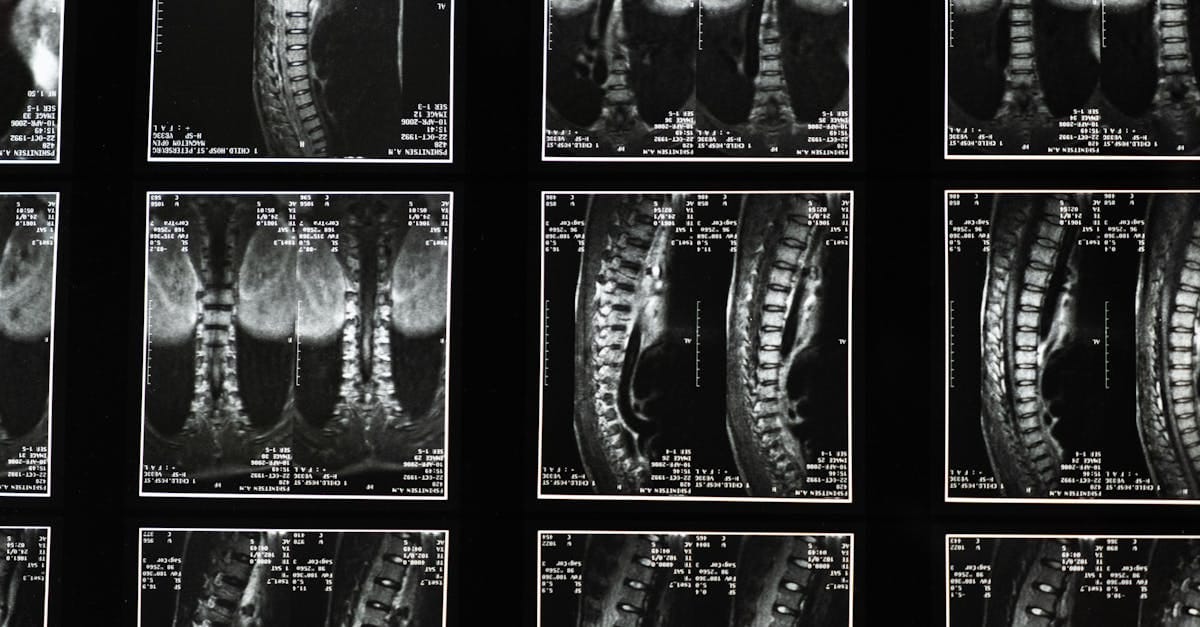

Un examen clinique approfondi et des imageries comme une IRM ou une radiographie sont souvent nécessaires.

Spinal decompression is based on a simple biomechanical principle: it involves the application of gentle forces on the spine, promoting the stretching of intervertebral discs. By creating space between the vertebrae, this treatment reduces pressure on nearby nerves. Consequently, blood circulation is improved, and the healing process of damaged tissues is optimized. Patients often report significant reductions in pain as well as improvements in their mobility.

Spinal decompression, although minimally invasive, requires a precise patient assessment before being proposed. The process begins with a comprehensive medical examination, followed by appropriate diagnostics to determine the severity of low back pain. Using specialized equipment, decompression therapy can be tailored to each patient, ensuring a procedure adapted to their unique needs. Thus, the results are often measurable, and patients notice significant improvements in their quality of life.